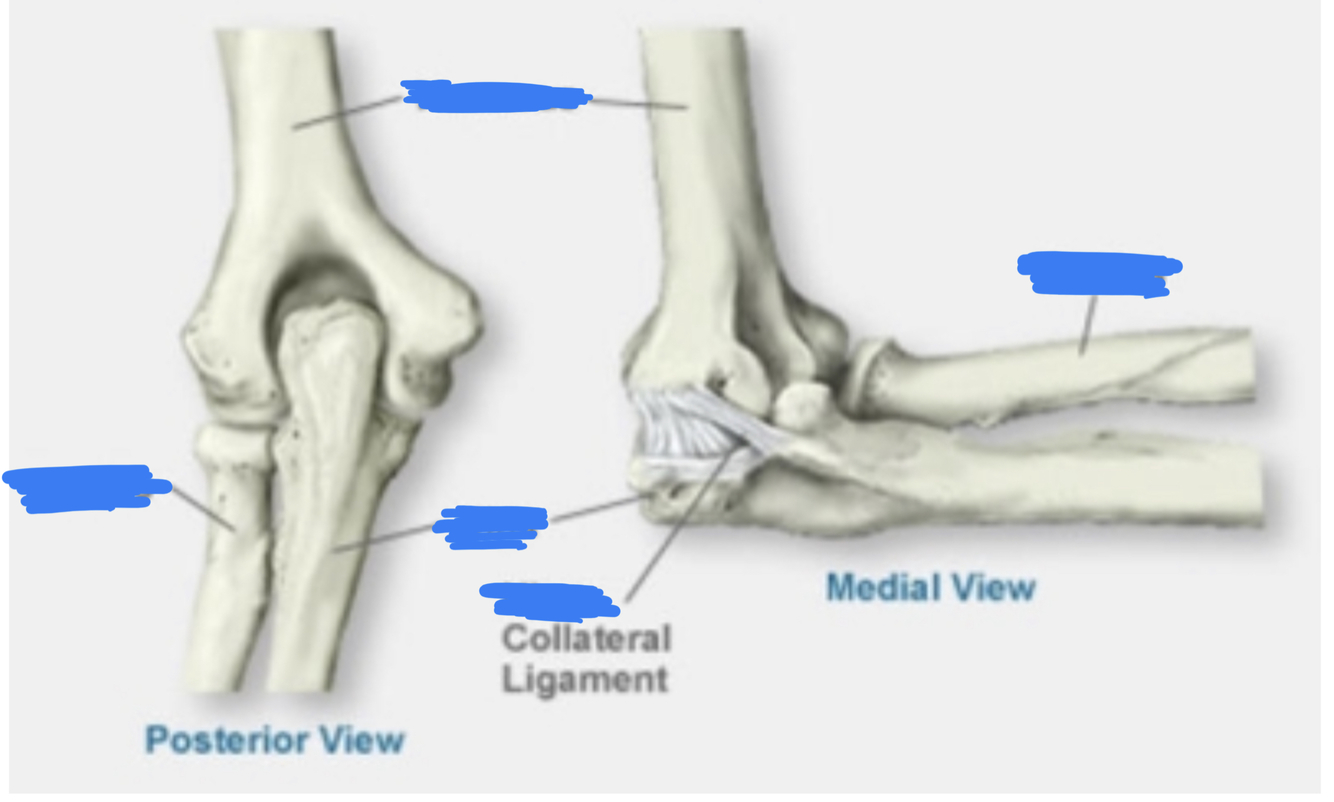

Ulna is bigger proximally, radius is bigger distally. Radius rotates, ulna doesn’t. The bones are held togeher by two radio-ulnar joints, proximally and distally.